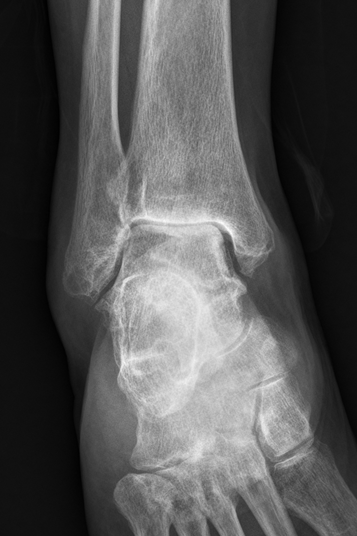

术前右踝关节片